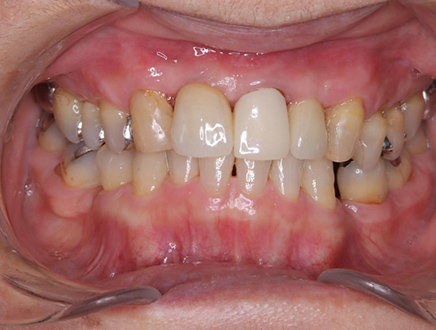

| 治療部位 | 上顎前歯部 |

|---|---|

| インプラント本数 | 4本 |

| 単価 | 40万円/本 |

| 合計費用 | 160万円 |